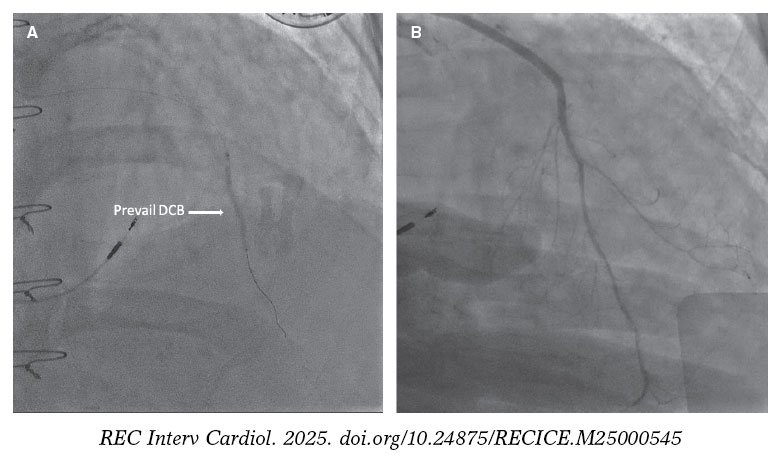

Afterwards, a Thrombuster II (Kaneka Corp., Japan) aspiration device was advanced into the mid LIMA. Contrast injection revealed an occlusion at the LIMA–LAD anastomosis (figure 1F, arrow). Although thrombectomy restored flow, severe stenosis persisted at the anastomosis site. Balloon angioplasty was performed, followed by the deployment of a 2.0 mm × 30 mm Prevail (Medtronic, United States) drug-coated balloon (DCB) across the graft and native LAD (figure 2A, arrow). Final angiography demonstrated excellent runoff (figure 2B; video 2), ST-segment resolution, and hemodynamic improvement.

Figure 2.